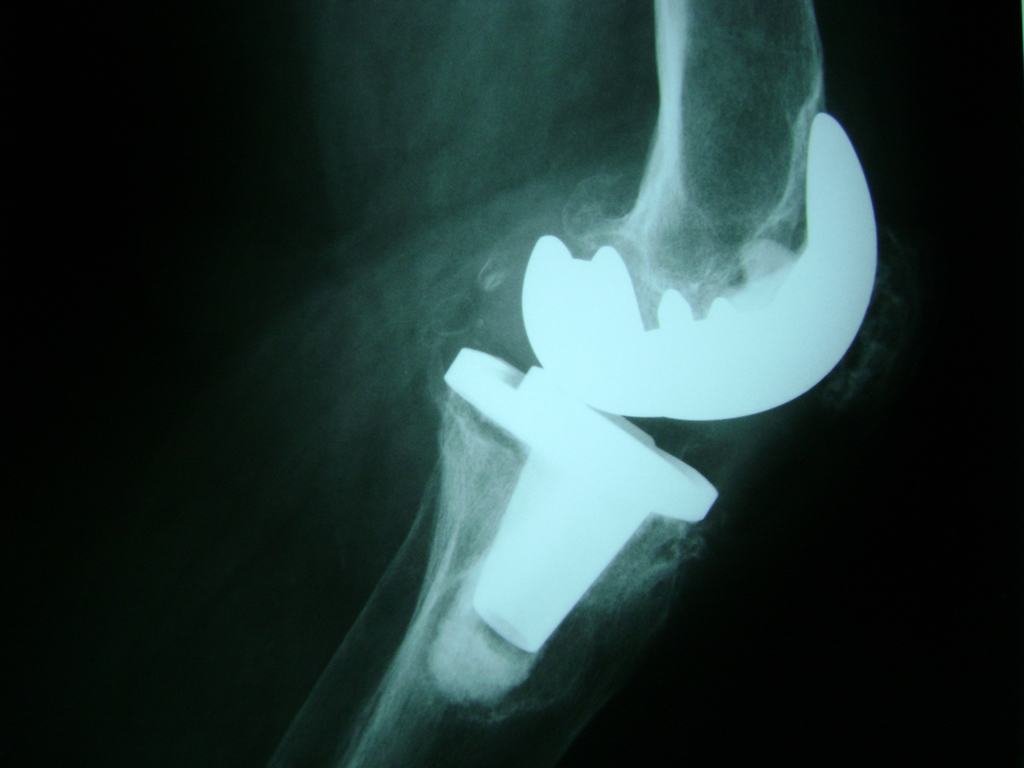

Cirugía de Fémur - Rodilla

La artroscopia de rodilla es un cirugía en el cual la estructura interna de la articulación es examinada ya sea para realizar un diagnostico o para realizar un tratamiento, este procedimiento se realiza utilizando un instrumento parecido a un pequeño tubo llamado artroscopio.